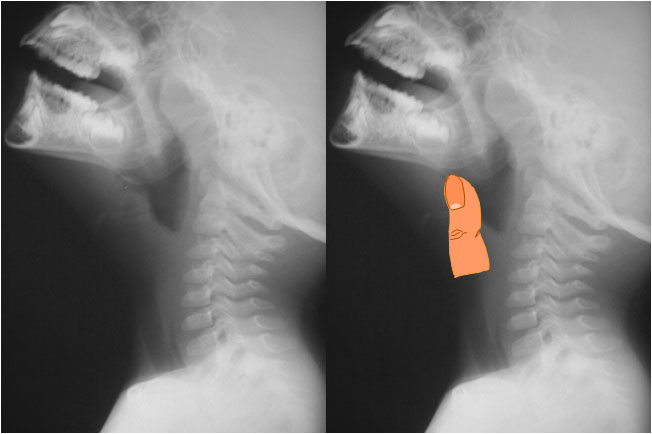

SIGNOS DEL PULGAR Y DEL MEÑIQUE

El Signo del pulgar es un signo de epiglotitis en la radiografía lateral de cuello. El engrosamiento de la epiglotis y de los repliegues ariepiglóticos tiene el aspecto y el tamaño aproximado de un dedo pulgar adulto. En la imagen de la izquierda puede verse el engrosamiento epiglótico y de los repliegues.

En cambio, en pacientes con dificultad de vías respiratorias altas de otro origen, el aspecto de la epiglotis es normal -como vemos en la imagen de abajo-, y se ha comparado con un dedo meñique (Signo del meñique).